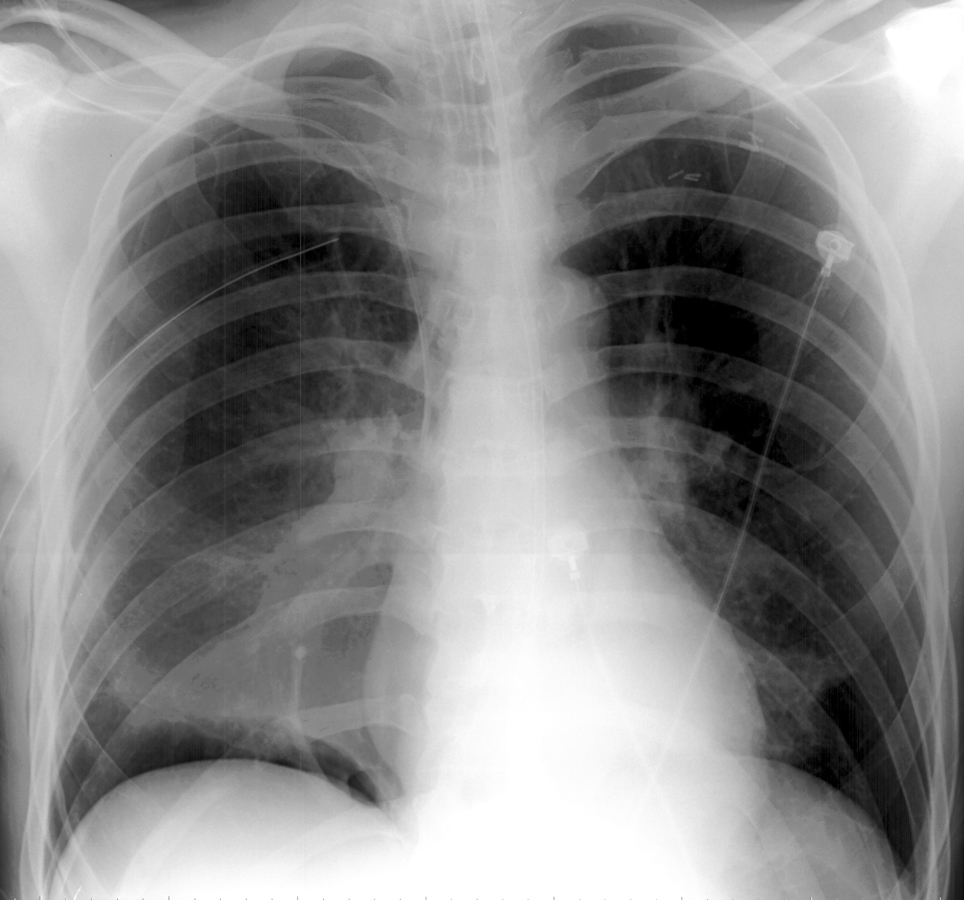

Anteromedial Pneumothorax

Anteromedial pneumothoraces are differentiated into those which are superior or inferior to the pulmonary hilum. A superior anteromedial pneumothorax may result in visualization of the superior vena cava or azygos vein on the right. An inferior anteromedial pneumothorax may be evidenced by delineation of the heart border and a lucent cardiophrenic sulcus. This is the key sign of a pneumothorax as this is the highest point in the supine patient, where the air will accumulate first.